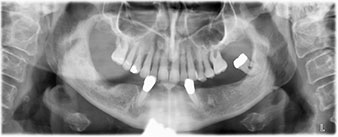

Para la planificación y la minimización del riesgo, se realizó una tomografía volumétrica tridimensional (TVD, Planmeca) que mostró que la calidad y la cantidad del tejido óseo era suficiente para la intervención quirúrgica y el tratamiento inmediato con el método Fast & Fixed. Siguiendo el protocolo de este método, se insertaron los implantes en la región de las piezas 35, 32, 42 y 45. Debido a la inclinación de hasta 45 grados de los implantes distales, el perfil de emergencia se desplazó hacia posterior y se generó un mayor polígono de soporte (fig. 3).

método Fast & Fixed

Fig. 3